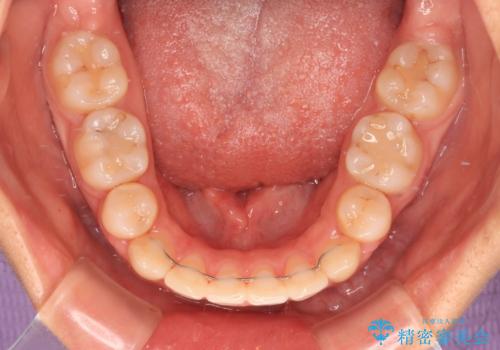

- 咬み合わせと、前歯のデコボコや八重歯、飛び出した口元を気にして来院された患者様です。

上顎は歯列不正が強く、右側臼歯部の咬み合わせは歯1本分ずれている状態でした。

補助装置を用いて奥歯の咬み合わせを改善しながら歯列を後方に移動させ、上下左右第一小臼歯を4本抜歯することで八重歯や口元の突出感を改善することとしました。

補助装置を併用したおかげでスムーズに奥歯の咬み合わせを改善することができ、我々も予想できないくらい理想的な仕上がりにすることができました。